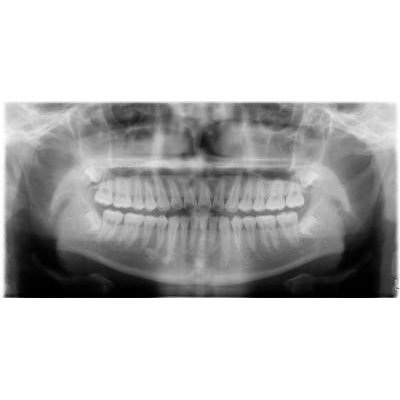

兒童牙科

商品大圖